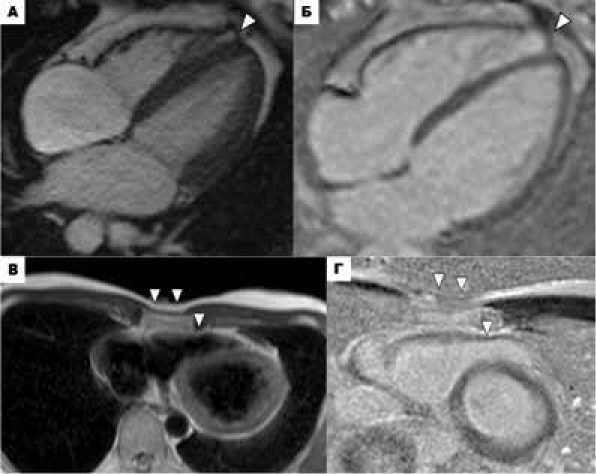

У пациентки № 840 по данным МРТ сердца выявлены микроаневризмы боковой и передней стенок ПЖ (рис. 4). У остальных пациентов с частой желудочковой тахиаритмией структурных изменений на МРТ не выявлено, и вероятно, ложноположительная интерпретация регионального дискинеза стенок ПЖ на МРТ обусловлено артефактами вследствие частой аритмии. При генотипировании этих пациентов у 4 (44,4%) из них были обнаружены варианты в генах, кодирующих ионные каналы: RYR2 (№ 766), CACNA1D (№ 1м), SCN1B (№ 834) и KCNE2 (№ 945); у 3 пациентов (№ 1м, 834, 945) – варианты в генах, ассоциированных с КМП ( TTN и CAVIN4 ).

Рисунок 4. МРТ сердца пациента № 840. Кино-изображения сердца в четырёхкамерной проекции в конечно-диастолическую (А) и конечно-систолическую фазу (Б), в проекции по короткой оси в конечно-диастолическую (В) и конечно-систолическую фазу (Г). Микроаневризмы боковой и передней стенок ПЖ (А, Б – белые головки стрелок, В, Г – чёрные головки стрелок), врожденный анатомический вариант.

Figure 4. Cardiac MRI of patient #840. Four-chamber cine images of the heart at end-diastolic (A) and end-systolic (Б) phases, and short-axis images at end-diastolic (В) and end-systolic (Г) phases. Microaneurysms of the lateral and anterior walls of the right ventricle (A, Б – white arrowheads, В, Г – black arrowheads), congenital anatomical variant.